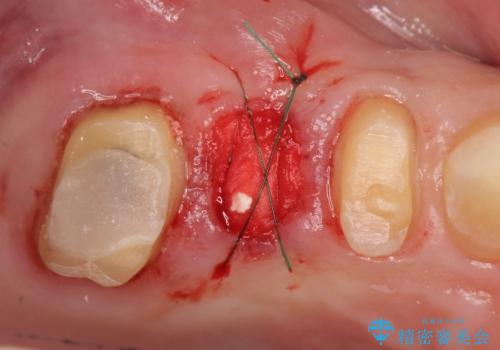

かぶせ(以下クラウン)を外してみたところ、神経のない支台となる歯が折れてしまい抜歯を余儀なくされる状況でした。

抜去後の機能回復方法としてインプラント、入れ歯以外の方法を希望されたためブリッジでの咬合機能回復を行っていくこととなりました。